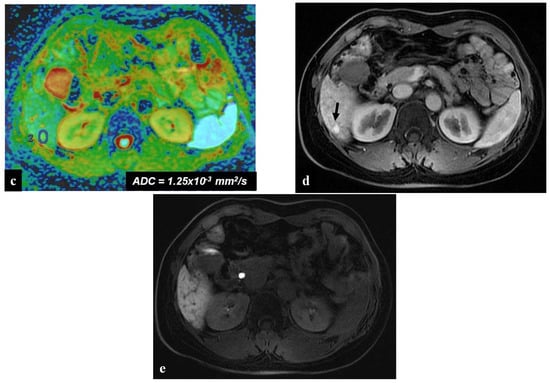

Figure 5.

(a–d) A 49-year-old man with hepatic metastases from colon cancer undergoing neo-adjuvant chemotherapy with folinic acid, 5-fluorouracil, oxaliplatin, and irinotecan (FOLFOXIRI) and with the association of bevacizumab. After chemotherapy, multiple small foci (arrow heads) appeared in the liver parenchyma, with the largest in segment 5 (arrow). This lesion was slightly hyperintense in the T2-weighted image (a) and presented slight restrictions in the DW-MRI image, with b-values of 1000 s/mm2 (b). The portal-venous phase (c) of the Gd-EOB-DTPA-enhanced MR image demonstrated inhomogeneous enhancement of the lesion, while in the hepatobiliary phase image (d), it appeared as a hypointense area. The biopsy of the largest lesion was diagnostic for peliosis.

Another uncommon focal liver lesion that may arise in the spectrum of oxaliplatin-induced sinusoidal damage is hepatic peliosis. This condition is pathologically characterized by multiple or occasionally solitary mottled blood-filled cyst-like spaces in the liver with associated sinusoidal dilatation [4]. MRI findings of hepatic peliosis depend on the stages of the blood component in these lesions. In T1-weighted images after contrast material injection, peliotic lesions usually show typical centrifugal enhancement (from the center to the periphery of the lesion); in DW-MRI, peliosis is characterized by hyperintense areas with similar diffusion restrictions to hemangioma, while in the MRI HB phase, these lesions appear as hypointense areas because the blood-filled cavities lack functional hepatocytes (Figure 5). However, some lesions may show central enhancement, which is suggestive of a spared, normal hepatocyte area [42]. Liver biopsy is indicated in case of doubt to differentiate liver metastases from peliosis.